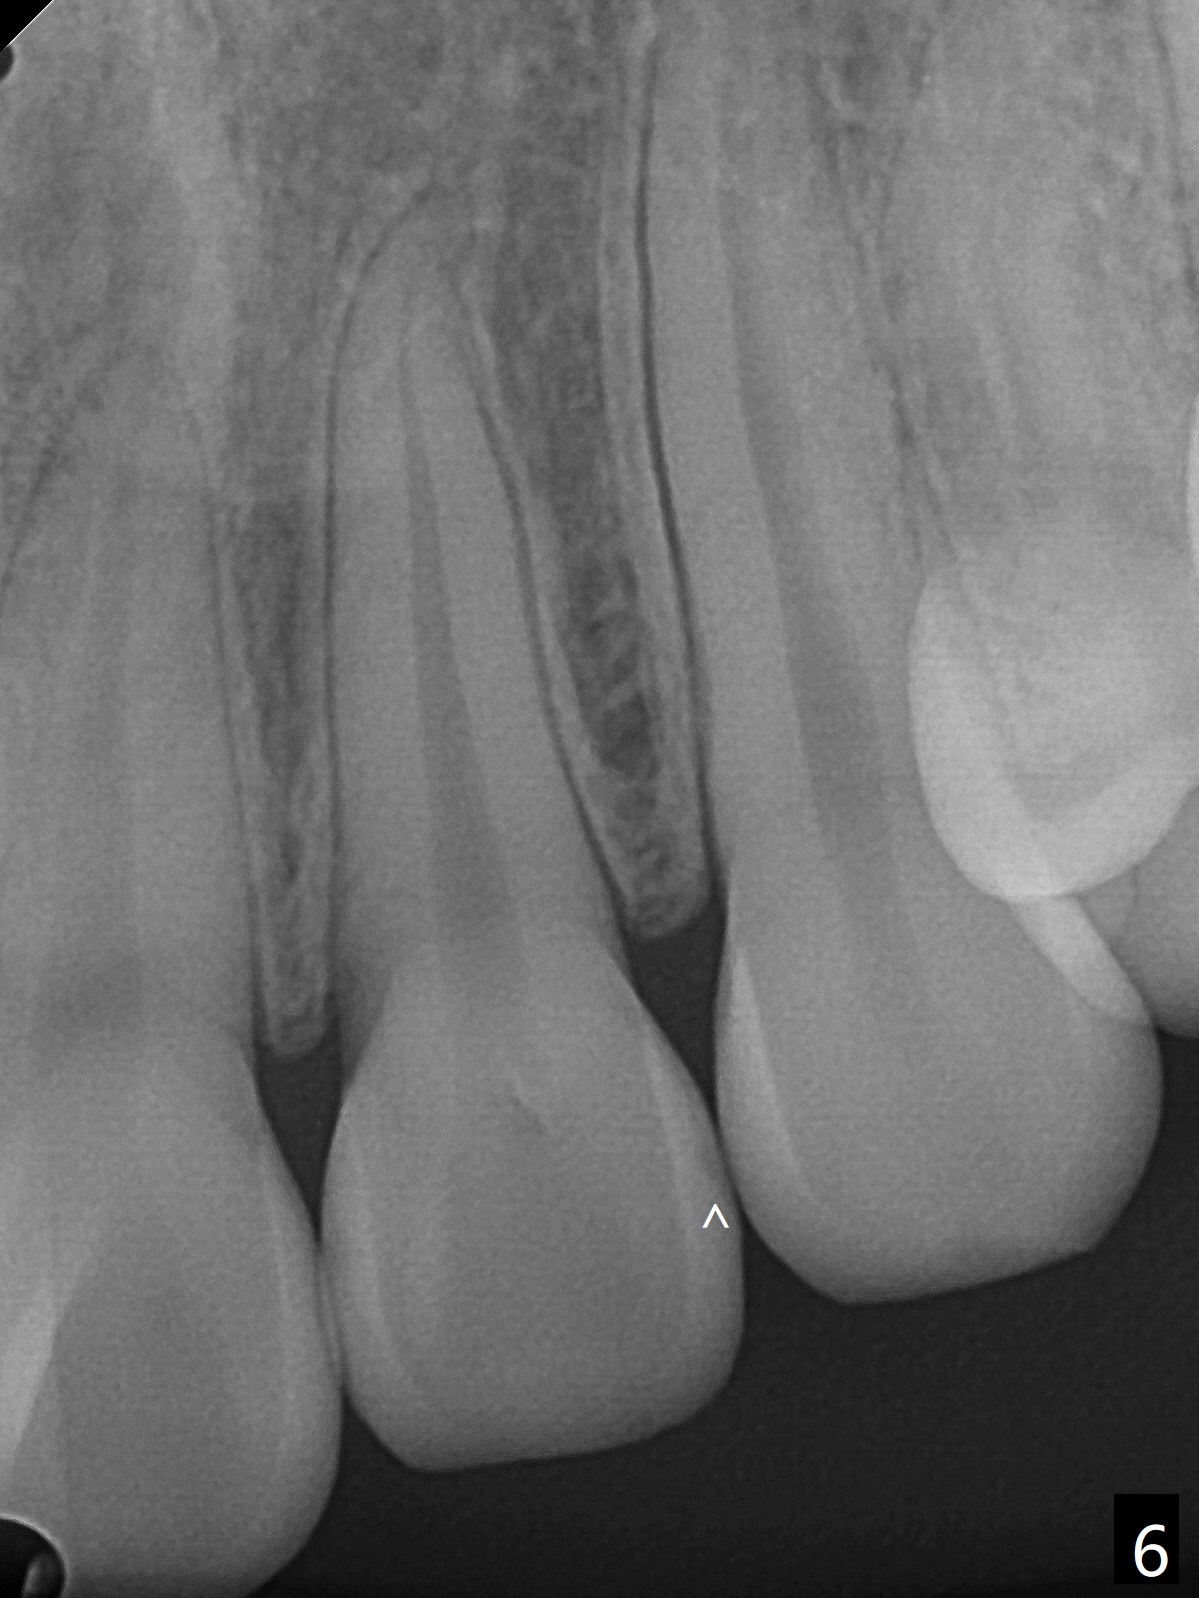

13岁女孩面型正常,先天性缺失右下1(图一,四,七),前牙深覆盖(图二),邻牙扭转(图三),治疗计划使用隐形矫正器,上牙片切,内收,关闭下切牙间隙(图八)。片切前发现上切牙邻面龋(图五,六),最大一个已经修补(右上2),不知其余小的龋坏能否片切,涂氟保守处理?不过她有龋坏易感性,以前乳牙龋坏。邻面片切后,上,下颌分别用无色和蓝色树脂做attachments(图九)。不明白的是Reciprocating saw远不如wheel利索。